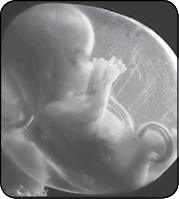

Начинают расти бровки, на голове пробиваются первые волосики, цвет которых может измениться после рождения. Малыш активно заглатывает амниотическую жидкость. Работающие почки выводят ее с мочой обратно в околоплодные воды. Появляются вкусовые ощущения. Наблюдаются дыхательные движения: малыш втягивает околоплодные воды в свои маленькие легкие и выталкивает их обратно. Он также начинает делать легкие толчки кулаками или пятками. Совсем скоро вы их почувствуете. Длина тельца 7–13 см, масса тела 45–50 г.

Будущий малыш хорошо двигается, но мама пока этого не ощущает. У него растут волосы, развиваются зубы. Ножки уже длиннее ручек. Через тончайшую кожицу видны ребра, кровеносные сосуды и сетчатка глаз. Хотя глазки прикрыты веками, малыш может чувствовать свет. Появляется лануго – тонкий пушок на тельце, который выполняет защитную функцию и поддерживает нужную температуру. Длина тельца 8–14 см, масса тела – 55–60 г.

Малыш уже размером с большую грушу. Растут ноготки на пальцах ног. Система кровообращения работает вовсю – в день маленькое сердечко перекачивает 24 литра крови. Оформившиеся косточки упрочняются и накапливают кальций. Голос мамы и бытовые шумы достигают полости матки. Появляется реакция на звук: малыш чувствует вокруг себя пульсирующий мир. Сформировались мышцы лица, поэтому у малыша теперь богатая мимика – он улыбается, корчит рожицы, хмурится и подмигивает. Ведет себя все так же очень активно: кувыркается, брыкается и уже может… играть. Его первая «игрушка» – пуповина, которую он хватает и тянет. За пуповину можно не беспокоиться: она очень прочная, но в то же время гибкая и приспособлена ко всем исследовательским манипуляциям малютки. Внешние половые органы сформировались настолько, что с помощью УЗИ можно определить пол будущего ребенка. Длина тельца 11–16 см, масса тела – 100 г.